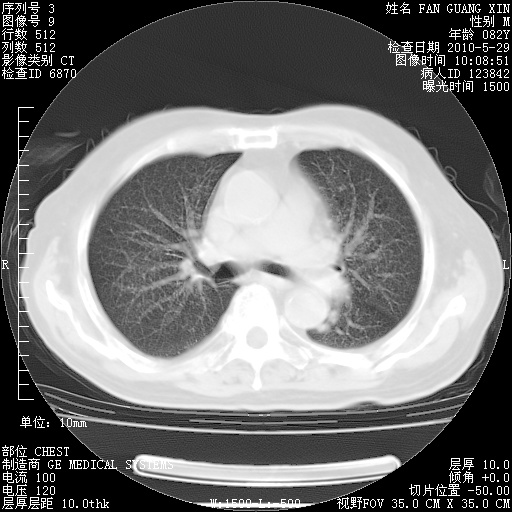

还需要哪些辅助检查?我们医院排除真菌感染没有任何检验方法,胸片好像能够排除肺部真菌感染。